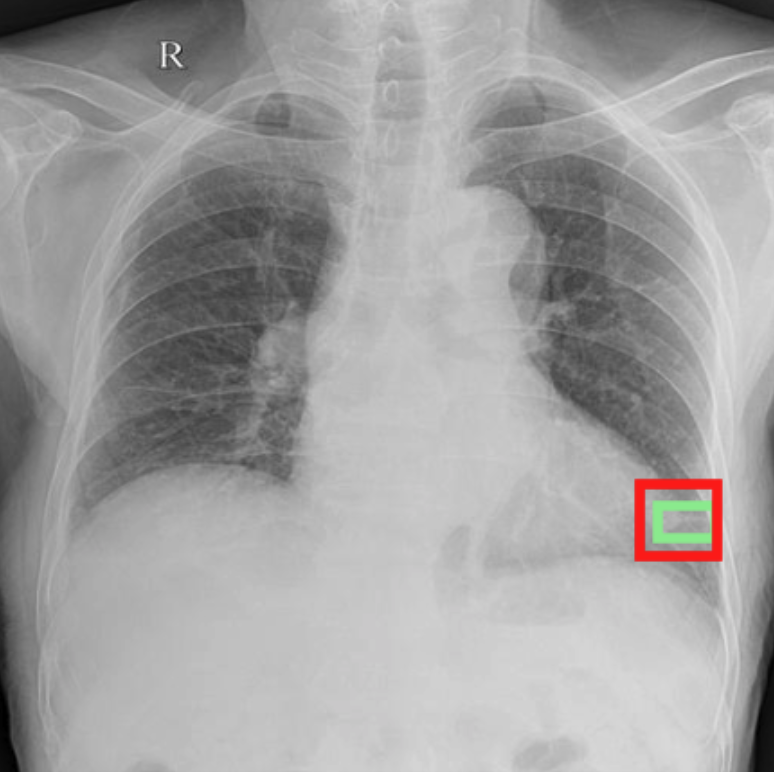

4.3.3 Visual grounding

In this section, we evaluate RadVLM’s visual grounding capabilities, which could help clinicians localize specific regions or pathologies on a CXR. This is particularly useful once a pathology has already been identified – either by a radiologist’s input or through our previously described AI tasks – since it allows one to pinpoint exactly where the abnormality appears on the image.

We report performance metrics for the three main grounding tasks RadVLM was trained on: anatomical grounding using the Chest Imagenome test set, abnormality grounding using the VinDr-CXR test set, and phrase grounding using the MS-CXR test set (Table 1). For each task, we use mean Average Precision (mAP) as our primary evaluation metric.

Our results show that RadVLM performs well at localizing anatomical regions (e.g., “right lung”, “aortic arch”, illustrated in Figure 5a), achieving a mAP of 85.8 %, by far surpassing the other CXR grounding models (Table 4). This advantage is partly explained by including the Chest Imagenome dataset (and thus the anatomical grounding task) in the training set, which CheXagent and MAIRA-2 did not leverage. However, it remains a key feature for any grounding model to possess a fine-grained understanding of CXR anatomy.

For the abnormality grounding task, RadVLM is less consistent (Figure 5b), likely due to higher sparsity of abnormality locations and labels, yet it still achieves best performance (Table 4). For the phrase grounding task, while MAIRA-2 and CheXagent demonstrate great performance, RadVLM surpasses them with a mAP of 81.8% (Table 4), presumably benefiting from the newly released PadChest-GR dataset (Castro et al.,, 2024) used for training.

Overall, these results show that our instruction tuning strategy for visual grounding (covering three essential tasks), combined to a modern VLM backbone, offers a promising avenue to help clinicians localize anatomical and pathological features during a CXR exam. Furthermore, providing fine-grained details within an LLM-generated output may also enhance the ability to answer grounded questions in a multi-turn setting, as we explore next.

b. Abnormality grounding

thickening

fibrosis

enlargement

lung disease

| Anatomical grounding | Abnormality grounding | Phrase grounding | |

| CheXagent | 6.2 | 26.0 | 69.7 |

| MAIRA-2 | 19.8 | 11.3 | 80.1 |

| RadVLM | 85.8 | 34.6 | 81.8 |